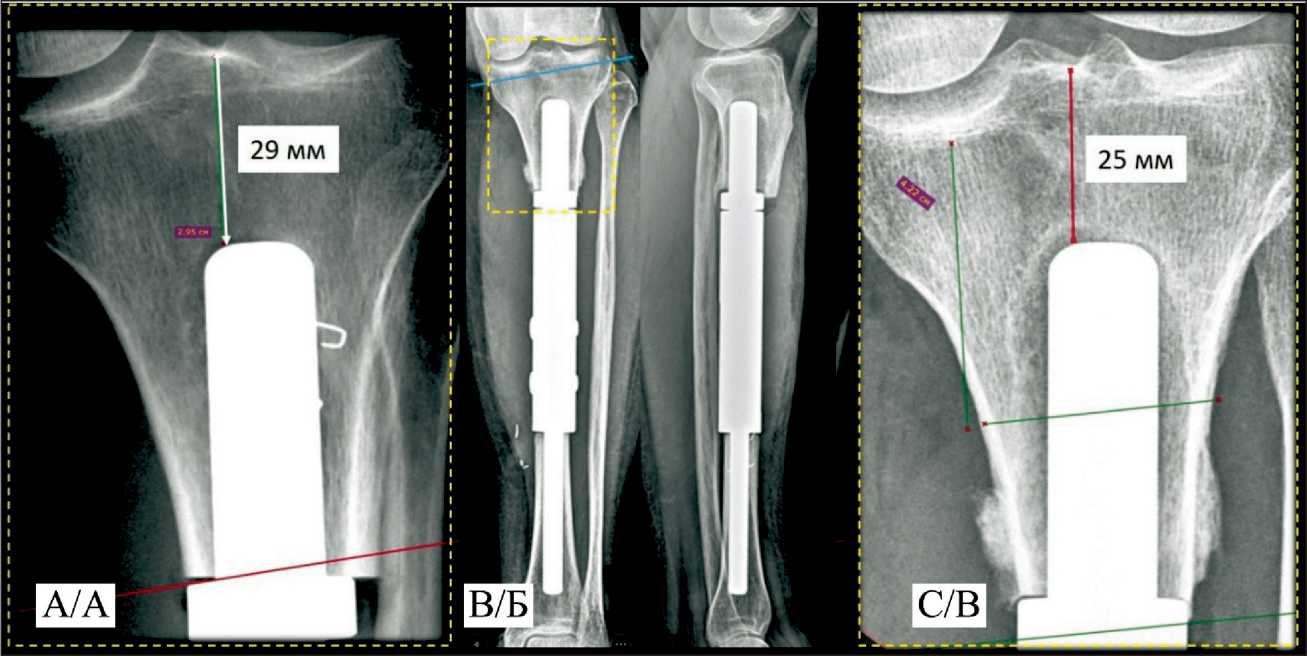

Fig. 4. A 52-year-old female patient. Osteosarcoma of the tibia diaphysis, T2N0M0; A – two days after custom-made endoprosthetic replacement. Post-operative x-ray; B, C – 3 month after surgery. Aseptic instability of the proximal stem, peri-implant bone lysis.

Note: created by the authors

Рис. 4. Пациентка Ч., 52 года. Диагноз: Остеосаркома диафиза большеберцовой кости, T2N0M0: А – 2-е сут после индивидуального эндопротезирования, послеоперационная рентгенограмма; Б, В – рентгенограмма 3 мес после операции. Асептическое расшатывание проксимальной ножки эндопротеза, периимплантный лизис костной ткани.

Примечание: рисунок выполнен авторами

In the second case, “Rekost” was used for the first time to fix a custom short-stem of the proximal component of a tibial diaphyseal endoprosthesis. However, three months postoperatively, aseptic instability of the proximal module developed, manifested by pain and gait disturbance (Fig. 4). The patient underwent revision surgery with replacement of the endoprosthesis component with a custom 3D-printed module.